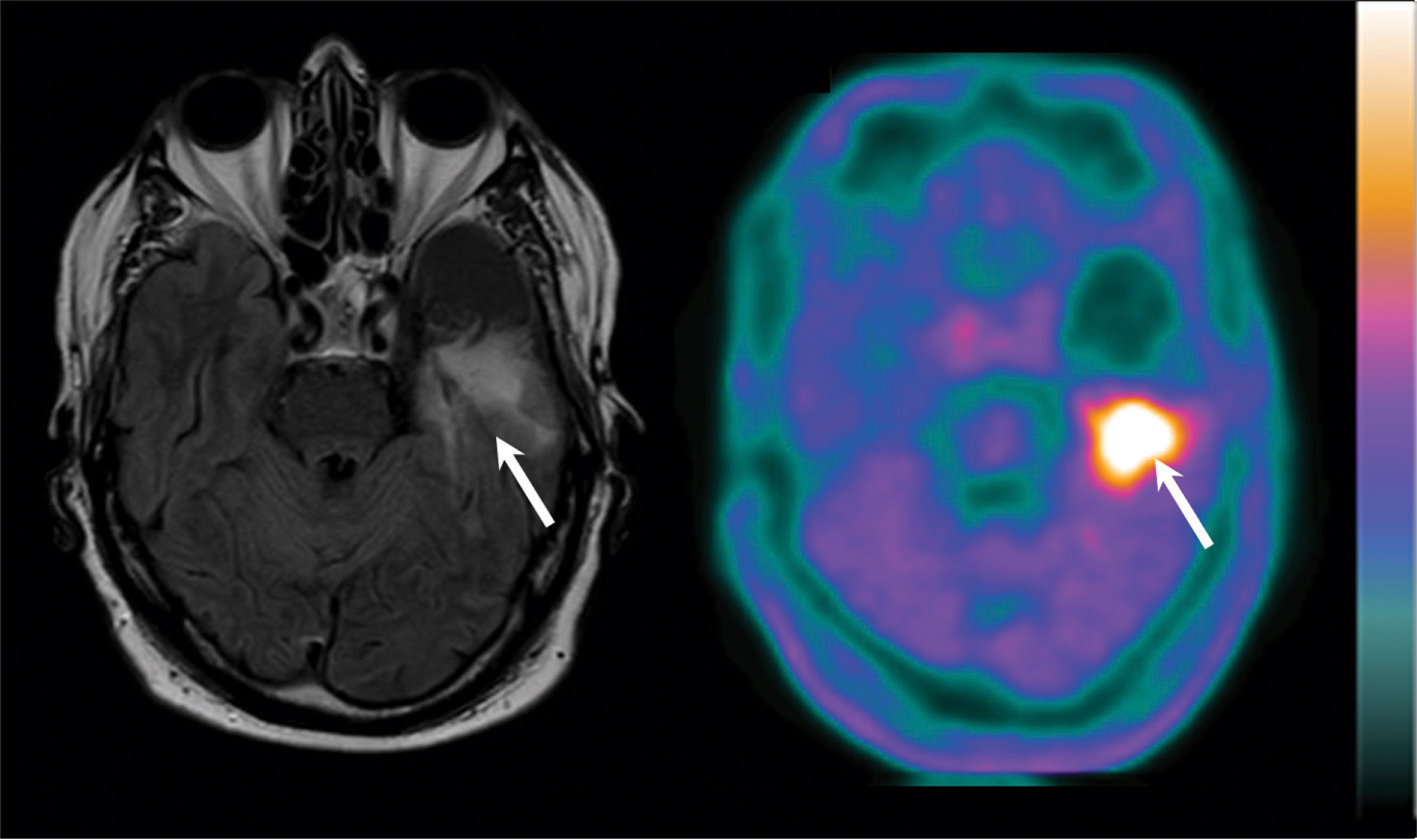

With regard to the differential diagnosis between tumor recurrence and radionecrosis, 11C-MET provides a better sensitivity and clearer delineation of the suspected recurrence (83). In a comparative study, 11C-MET was found to be superior to 18F-FDG for diagnostic accuracy in distinguishing glioma recurrence from radiation necrosis (95). Similarly, in a prospective comparison with 18F-FDG PET, 18F-FDOPA PET had a diagnostic accuracy of 100% for the diagnosis of glioblastoma recurrence versus 92.8% with 18F-FDG PET (96). In addition, in a study of 110 glioblastoma patients, 18F-FDOPA PET detected recurrence with high accuracy while lesion-to-normal-tissue ratios were predictive of progression-free survival (97). Finally, 18F-FDOPA PET is also able to distinguish tumor recurrence from treatment-related changes (24), an example of which is depicted in Figure 4. In a similar manner, static and dynamic 18F-FET PET parameters can differentiate progressive or recurrent glioma from treatment-related nonneoplastic changes with a higher accuracy than conventional MRI, especially with regard to glioblastoma recurrence (98, 99).

Fig 4

Figure 4 Left temporal glioblastoma recurrence in a 66-year-old man after surgery and adjuvant radiochemotherapy. The axial slice of Fluid-Attenuated Inversion Recovery (FLAIR)-weighted MRI (left side) shows a hypersignal at the posterior area of the exeresis cavity (white arrow), making the distinction between tumor recurrence and post-therapeutic effects somewhat challenging. The axial slice of 18F-FDOPA PET shows an intense uptake in the same area (white arrow), which is strongly in favor of tumor recurrence.